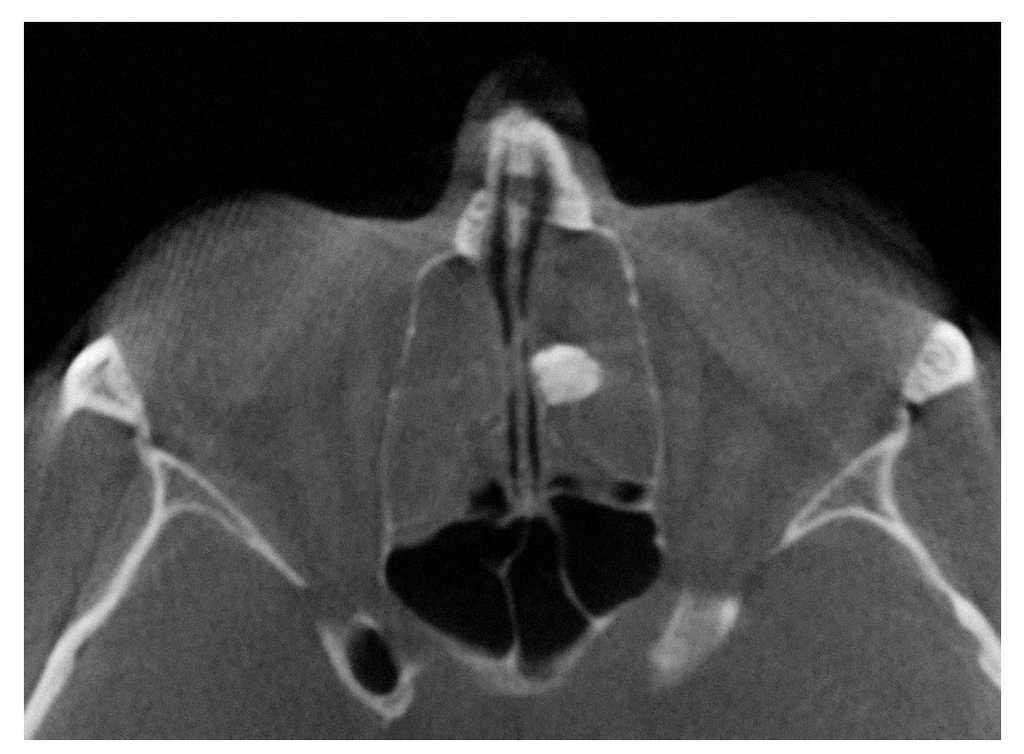

En la visita a nuestra clínica el paciente refirió un dolor en la zona del seno maxilar izquierdo. En la radiografía panorámica practicada se observó un seno maxilar izquierdo completamente velado y un engrosamiento de la mucosa basal en el seno maxilar derecho (fig. 1). Se identificaron además diversos dientes que requerían tratamiento odontológico. Debido al gran malestar del paciente, se realizó una tomografía volumétrica digital dental (TVD) para el estudio diagnóstico de los demás senos paranasales.

Figura 1. Radiografía panorámica.

En la TVD se observa un seno maxilar izquierdo íntegro y homogéneamente ocupado, además de una obstrucción del ostium fisiológico en ambos lados. Se aprecia también una opacificación subtotal de todo el complejo etmoidal y también del seno frontal. Estos hallazgos sugieren un diagnóstico de mucocele del seno maxilar izquierdo y de pansinusitis de los senos paranasales. En el lado izquierdo, en la zona de las celdas etmoidales superiores se observa una masa circunscrita de densidad similar a los tejidos duros junto con una obstrucción parcial de las celdas etomoidales izquierdas. Se trata probablemente de un osteoma.